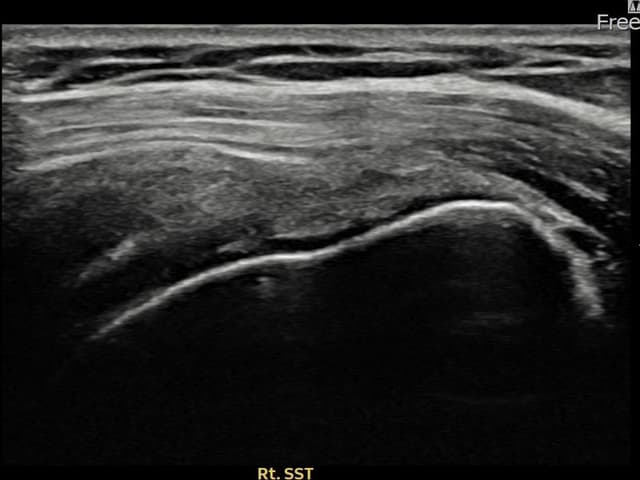

[経過期間: 23.09.19~23.11.21]

[縫縮術] 超音波検査にて右 棘上筋腱 関節面側部分断裂(9mm × 4mm (腱厚の約38%欠損))を確認。縫縮術施行後、腱の連続性が回復し、日常生活に復帰されました。